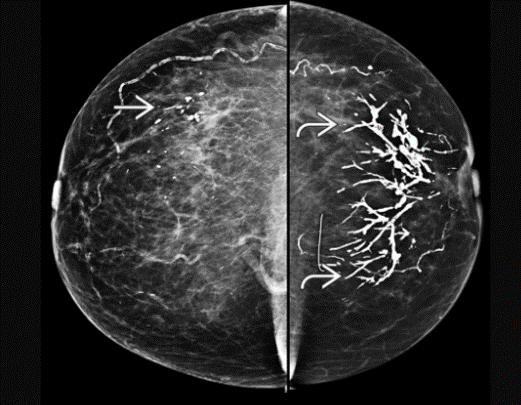

fine pleomorphic

= scary

BR 4 or 5

segmental fine pleomorphic calcs. BAD!

BR 5